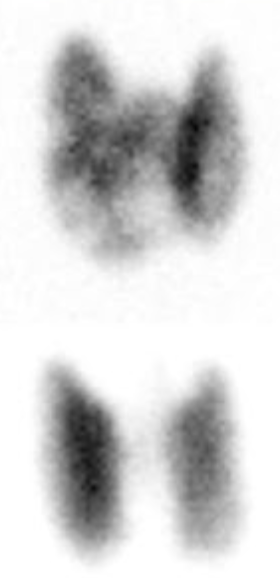

Q

Elderly female with weight loss, anxiety, and tachycardia

A

Think toxic multinodular goiter (AKA Plummer disease)

Note: Heterogeneous thyroid uptake (Graves would be homogenous, see lower image).